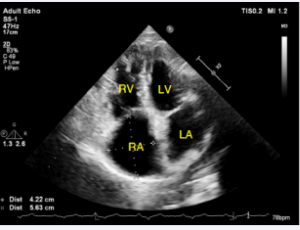

AbstractUnroofed coronary sinus is a rare subtype of atrial septal defect, which is an adult congenital heart disease characterized by communication of the systemic and pulmonary circulations at the atria level. We describe a 25-year-old female with a rare c.....